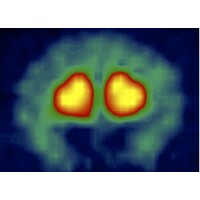

➤ OUR MISSION: Our mission at Neuro Regenerative is to improve the health and quality of life of individuals with neurological or sleep disorders. ➤ WHAT WE DO: We provide expert care and personalized treatment for individuals with neurological or sleep disorders through endovascular stem cell therapy. Our goal is to help our clients achieve optimal health and a better quality of life. ➤ HOW WE DO IT: This innovative procedure involves injecting stem cells directly into the bloodstream through a small catheter inserted into a blood vessel. The stem cells then travel to the targeted area of the brain or spinal cord, where they work to repair damaged tissue and stimulate the growth of new cells. We can help you: ✔ Relieve symptoms of head trauma: Our endovascular stem cell therapy repairs damaged tissue and stimulates new cell growth, improving strength and quality of life. ✔ Enhance athletic performance: Our treatment improves overall health and wellness, helping athletes reach their full potential. ✔ Improve mental health: By addressing underlying conditions and improving overall health, we help our clients live happier and more fulfilling lives. ➤ WHAT MAKES US DIFFERENT: We are the only team in the world offering endovascular stem cell therapy for the treatment of head trauma. Our specialized focus in this niche allows us to deliver the highest level of expertise and care to our clients. To make the process as smooth as possible for our clients, we offer a patient concierge service that handles all the details, from scheduling appointments to coordinating travel and accommodations. We are located in Panama, where it is legal to perform endovascular stem cell therapy, and we use only the highest grade organic stem cells to ensure the best possible outcomes. In short, our commitment to excellence and personalized care sets us apart in the world of head trauma treatment.